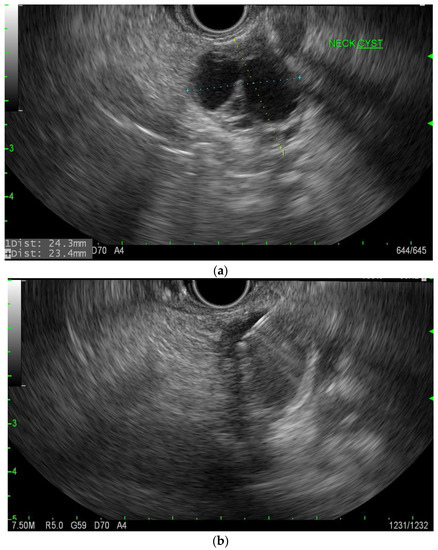

MCNs usually present in the fifth to seventh decade of life and are almost exclusively in females. Typical imaging characteristics consist of unilocular or septate cysts with wall calcifications (Figure 1). MCNs are defined as having ovarian-type stroma with mucin production. A solid component may suggest malignancy [9]. The aspirate is usually viscous, and the cytology findings consist of columnar cells with variable atypia. On cytology, if cells are present, there are columnar cells with stains positive for mucin. CEA is usually >200 mg/mL in approximately 75% of lesions, and the typical glucose level is usually less than fifty [10]. In a study of 90 resected MCNs, only 10% contained either high-grade dysplasia or pancreatic cancer; however, the reported rate of malignancy ranges from 0 to 34% [11,12,13,14].

Figure 1.

EUS image of the mural nodule (labeled solid component) in a mucinous cyst.